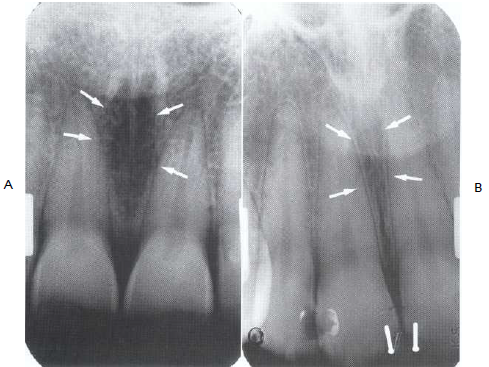

37. What is the anatomical structure indicated by arrow in this radiograph?

38. What is showing by arrow?

39. What is showing by the arrow?

40. Which anatomical structure is indicated by the black arrow?

41. What is the anatomical structure indicated by arrow in this radiograph?

42. What is the anatomical structure indicated by arrow in this radiograph?